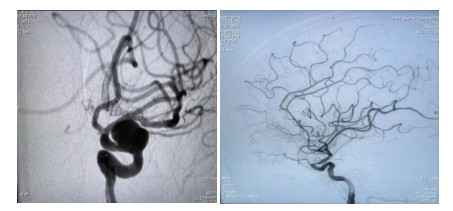

原來64歲的羅奶奶因為發(fā)現(xiàn)頸動脈瘤10余天,來到衡陽市中心醫(yī)院全科醫(yī)學科住院,在完善腦血管造影檢查后,診斷其為左側頸內(nèi)動脈眼動脈段動脈瘤,瘤體大,并有分葉子瘤,為高危破裂動脈瘤。危急之下,轉(zhuǎn)入神經(jīng)內(nèi)科一病區(qū)準備進行介入手術治療。

經(jīng)過充分的術前準備工作,神經(jīng)內(nèi)科中心主任丁菁帶領介入團隊與導管室、麻醉科等多學科共同協(xié)作,順利為羅奶奶實施了血流導向密網(wǎng)支架輔助下顱內(nèi)動脈瘤栓塞術。手術過程順利,術后羅奶奶在麻醉蘇醒后安返病房。在神經(jīng)內(nèi)科一病區(qū)醫(yī)護人員的精心護理下羅奶奶恢復良好,順利出院。

介入治療動脈瘤,是目前國內(nèi)外大中心治療動脈瘤的主要方法。最常見是把動脈瘤腔用微彈簧圈進行填塞,使瘤腔內(nèi)形成血栓達到動脈瘤的致密栓塞、解剖治愈的目的。對于有一些大的動脈瘤瘤頸非常寬,栓塞后仍有很高的復發(fā)率??梢圆捎醚鲗蜓b置,也就是密網(wǎng)支架治療動脈瘤。它是最新的治療方法,我們的羅奶奶就是采用這種治療方法。

密網(wǎng)支架又被稱為血流導向裝置,是一種新型的介入栓塞材料。它在血管內(nèi)跨過動脈瘤釋放支架。由于這個支架的網(wǎng)眼非常小,導絲非常細,會干擾并減少從載瘤動脈進入動脈瘤的血流,使動脈瘤中血流出現(xiàn)阻滯,導致動脈瘤內(nèi)血栓形成,表現(xiàn)為“血流導向”作用;同時它提供血管內(nèi)皮細胞攀爬生長的腳手架,促進內(nèi)皮化修復。它較彈簧圈栓塞操作更簡便,手術風險降低,更安全。